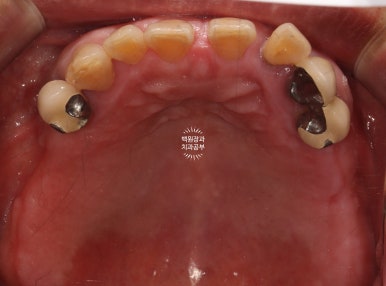

구강내 교합면 사진입니다.

파노라마 엑스레이상에서 많은 치아가 있어보이지만,

실제로 대부분의 치아는 많은 양의 치석이 침착되어 만성치주염의 주소견인 흔들림을 보여주고 있었습니다.